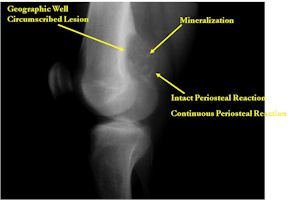

Plain X-rays:

- Geographic, circumscribed lesion usually around 5cm in size.

- There may be expansion of bone, cortical thinning and cortical breakthrough. A soft tissue mass may accompany this lesion but the soft tissue component is usually contained by the periosteum.

- The periosteum remains intact around the soft tissue component. Might need a CT scan to detect the subtle calcification (Egg Shell Rim of Calcification) associated with an intact periosteal reaction

- The lesion may be entirely radiolucent but usually shows some degree of mineralization. Mineralization may appear stippled like cartilage but do not see chondroid pathologically. Mineralization is sometimes better detected on a CT scan rather than an x-ray.

- Usually less surrounding sclerosis than an osteoid osteoma.

- Arise from the Diaphysis (75%) more commonly than Metaphyseal (25%)

- 4 cm to 6 cm in size